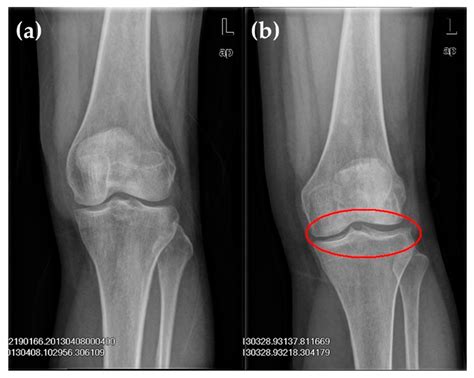

What Does a Normal Knee Xray Look Like?

A radiologist interprets a knee X-ray by looking at several key anatomical landmarks. When a report comes back as a normal knee xray, it means the technician and radiologist have observed the following components as being within standard clinical limits:

• Bone Integrity: There are no visible breaks, hairline fractures, or bony abnormalities.

• Joint Space: The gap between the femur (thigh bone) and the tibia (shin bone) is symmetrical and maintained, which suggests that the articular cartilage has not significantly eroded.

• Alignment: The bones are in their proper anatomical position, indicating there are no major dislocations or congenital malalignments.

• Soft Tissue Shadows: While X-rays are primarily for bones, they can sometimes show swelling or fluid accumulation (effusion) around the knee joint.

Because X-rays primarily capture dense tissue, a "normal" result confirms that the structural framework of your knee is intact. This is excellent news if you were concerned about a broken bone or severe bone deformity.